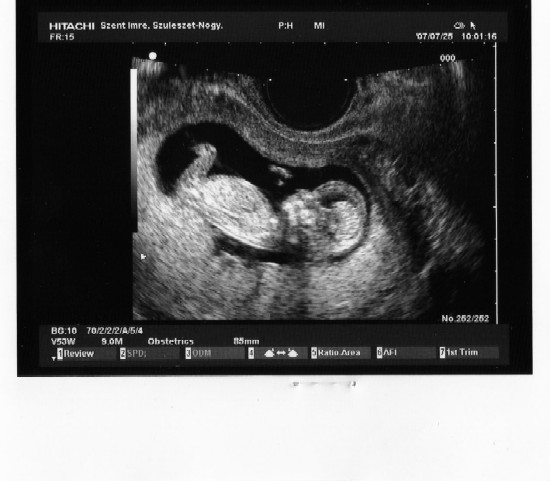

Neked is nagy-nagy gratula!

Rosszullétet sajnálom, de nem biztos ám, hogy kislány. A nővéremnek három fia van, az első kettővel semmi baja nem volt, a kicsivel úgy hányt, mint a lakodalmas kutya, közben a nagyobbak sírva csimpaszkodtak a lábába, mert azt hitték, hogy komoly beteg. Kislányt szeretnétek? Alkalmaztatok valami "trükköt" hozzá?

Keve is nagyon bújós lett, már akkor, mikor mi még nem is gondoltunk rá, hogy baba van a dologban. Én nagyon élvezem, mert eddig én csak úgy el voltam viselve.